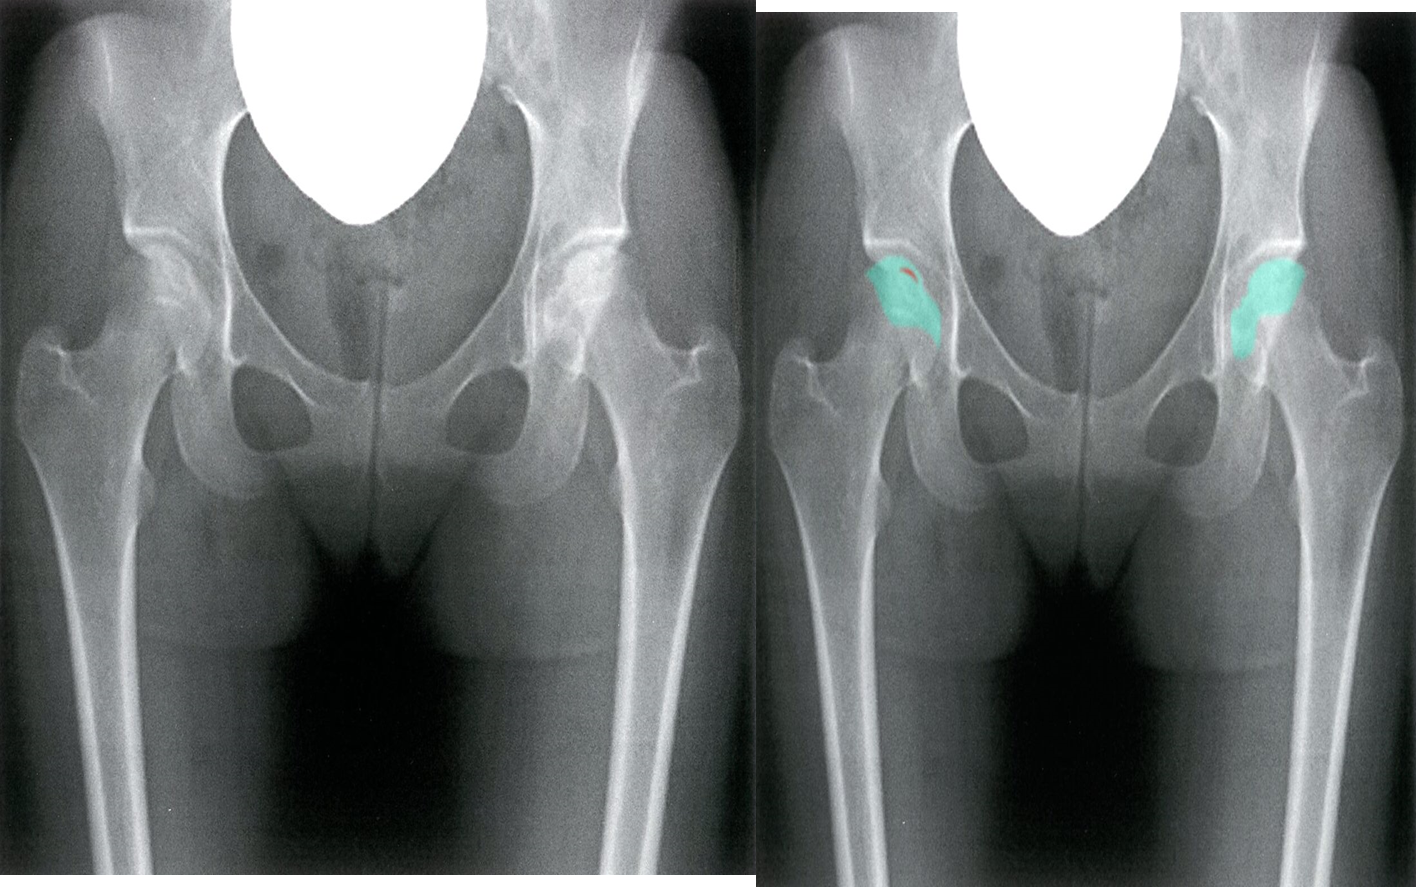

Plain radiograph:

- There is initial minor osteopenia, followed by sclerosis and rim calcification. Gradually microfractures leading to the collapse of the articular surface.

-20240312222223436.webp)

Bilateral femoral head avascular necrosis

X-ray pelvis (anteroposterior view) Increased density of the femoral heads (green overlay) is accompanied by articular surface irregularity and subchondral lucency (crescent sign; red line overlay).